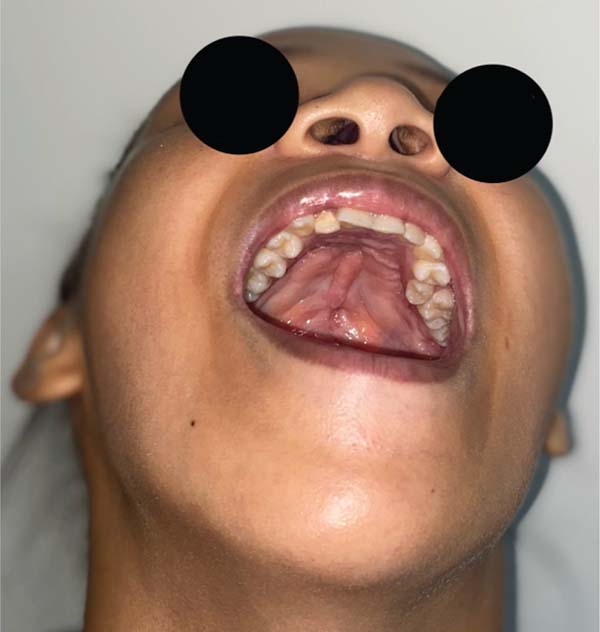

Uma análise adicional revelou que um dos pacientes apresentava um distúrbio comportamental com movimentos repetitivos mão-boca, conforme relatado pela mãe. No segundo caso, foi observada uma fossa velopalatina nas fotos pré-operatórias, e uma dissecção inadequada contribuiu para a formação da fístula pelo cirurgião (►Figs. 4–11).

Os casos de fístula na Zona II foram analisados, e identi-ficou-se um distúrbio comportamental em um dos casos, com diagnóstico de autismo leve e relatos maternos de movimentos repetitivos mão-boca. No segundo caso, uma fossa velopalatina foi notada nas fotos pré-operatórias, o que indicava dissecção inadequada como causa da fístula. É crucial analisar individualmente os casos de FON para entender os fatores contribuintes e aprimorar a abordagem cirúrgica para reduzir sua incidência.